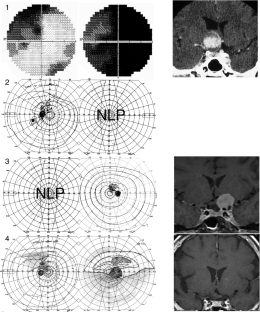

The hemi-decussation at the optic chiasm creates the potential for crossed and uncrossed fibers to be affected in isolation or in various combinations of nerve, chiasm and tract, with patterns that reflect the retinotopic arrangement of axons. We present seventeen cases that illustrate the field defects that can result and review the literature to create a taxonomy of junctional visual field defects. The complete junction defect is blindness in one eye and loss of the entire temporal field of the other. The classic junctional scotoma combines optic neuropathy in one eye with upper temporal hemifield loss in the other, and is often a sign of ventral compression. The less frequent atypical junctional scotoma involves the lower temporal hemifield and has a higher frequency of dorsal compression or non-compressive pathology. There are the monocular defects in the temporal (‘junctional scotoma of Traquair’) or nasal hemifield, the latter of which is rarely if ever due to a pituitary adenoma. Highly asymmetric bitemporal defects with or without a central scotoma and the paradoxical junctional scotoma occur by extension of the lesion causing the junctional scotoma of Traquair. The posterior junction defect results from combined damage to the optic chiasm and optic tract. Recognizing these various patterns is important clinically as junctional defects have the same localizing significance as bitemporal defects and are being encountered more often. In addition the probability of certain types of pathology varies with the type of junctional defect.

Figures in cases 1, 6 and 12 are adapted with permission from: Barton JJS, Benatar M. Field of Vision: a manual and atlas of perimetry, Humana Press (now Springer Nature), Totowa NJ, 2003, and those of cases 7, 9 and 15 are reproduced with permission from www.neuro-ophthalmology.ca. We thank Briar Sexton for sharing case 9 with us.

Barton, J.J.S., Özturan, G. The varieties of junctional scotoma: 17 cases, a review, and a taxonomy. Eye 39, 1673–1687 (2025). https://doi.org/10.1038/s41433-025-03789-z